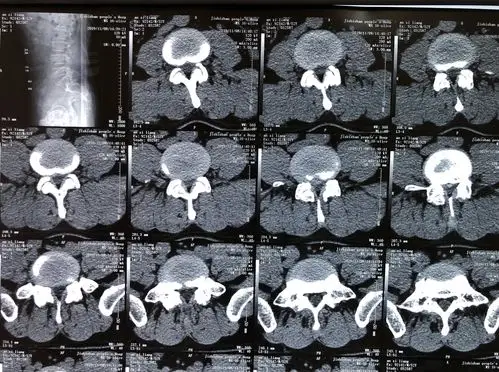

腰椎间盘突出症

腰椎间盘突出症患者相关资料

一区新入13床,陈广梅,女,66岁,腰椎间盘突出症,腰椎滑脱.

腰椎ct 磁共振显示,腰4/5椎间盘突出,神经受压粘连